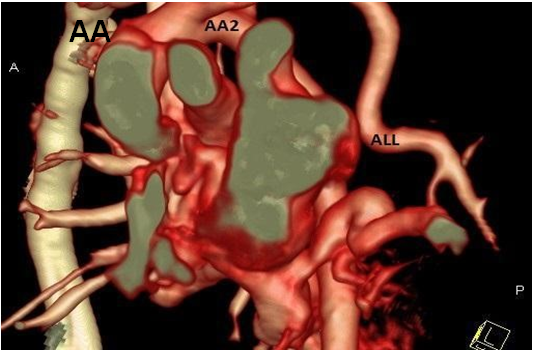

AUL, Absent Lt Upper Lobe; LLB,  Lt. Lower Lobe Bronchus;   ALL, Aberrant artery from the aortic arch supplying Lt. Lower Lobe;  L, hyperinflation of contralateral lung; LLL, Lt. Lower Lobe.

With a suspicion of Lt lung agenesis, a high resolution contrast enhanced CT scan was ordered. This showed agenesis of the Lt upper lobe, a rudimentary Lt lower lobe and an aberrant artery from the aortic arch supplying the left lower lobe. This was consistent with a Type 3 of lobar agenesis, and hypoplastic, ipsilateral pulmonary artery with normal bronchus of the lower lobe. An aberrant systemic arterial supply to lower lobe was an additional finding.

At 4 months of age, the child underwent a left thoracotomy and the aberrant artery from aorta was re implanted into the pulmonary artery, thus restoring the pulmonary blood supply to the left lower lobe. Should this procedure was not possible, the child would have had removal of the left lower lobe.